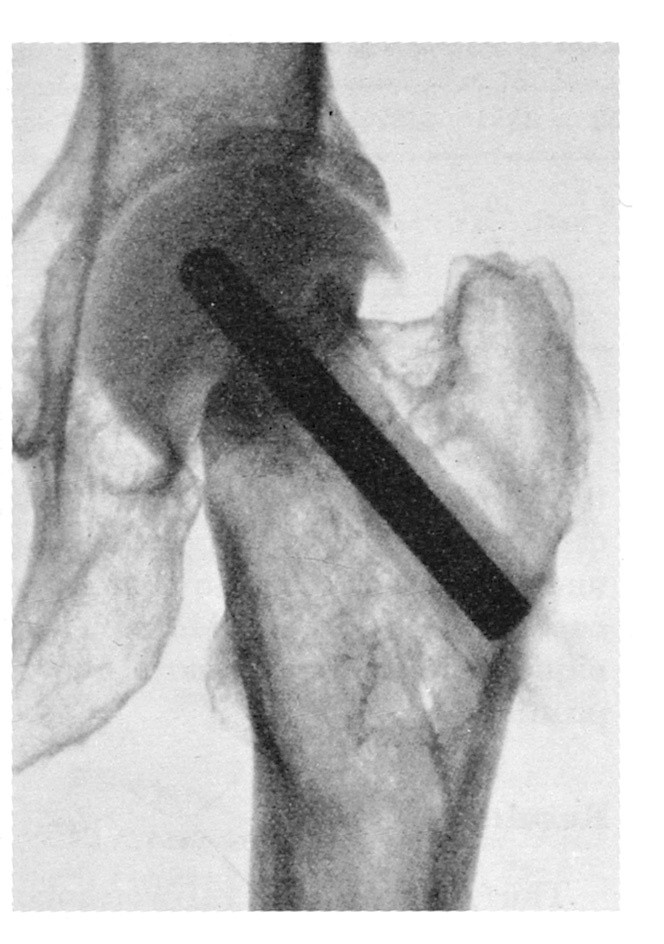

Prothese: Judets Prothese

Judets Prothese

Judets Prothese mit Schenkelhalsstreckung (Anfang der 50er Jahre).